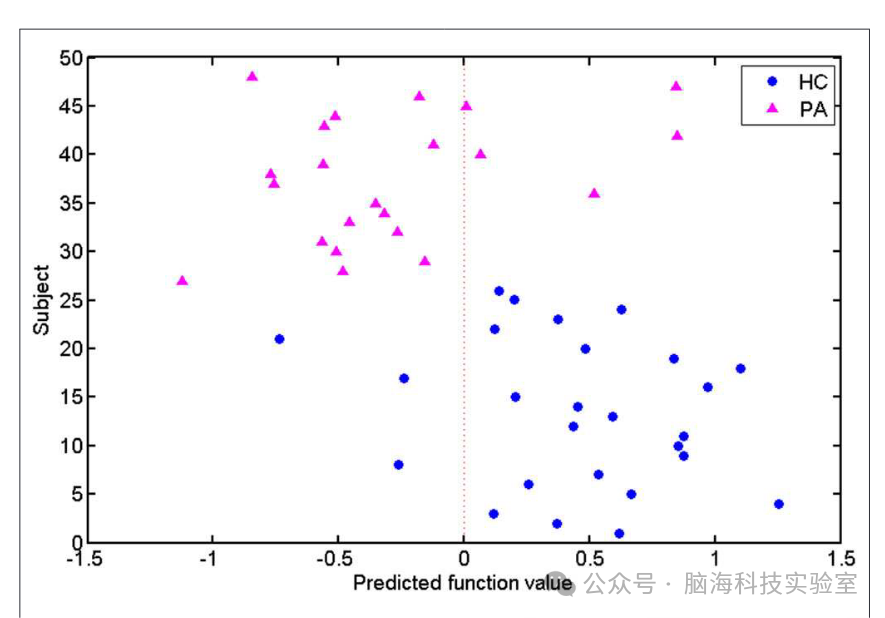

此外,研究利用SVM分类器获得了每个测试受试者的预测函数值(见图4)。圆形和三角形分别代表健康对照组(HC)和患者。右侧的圆形表示被正确分类为健康对照组的受试者,而左侧的三角形表示被正确分类为患者的受试者。根据这些点的分布,研究发现大多数受试者(40/48)被分类器正确分配了标签。

图4